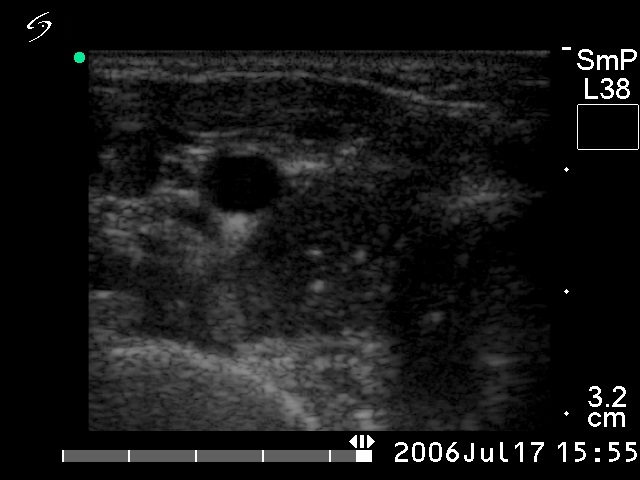

Ultrasonography: The right lobed was composed of a hypoechogenic nodule with hyperechogenic foci. The latter were greater than foci of a microcalcification and did not exhibited acoustic shadow. This is the typical appearance of an amyloid deposit. The left thyroid contained a similar tumor. There was a metastatic lymph node in the right side of the neck.